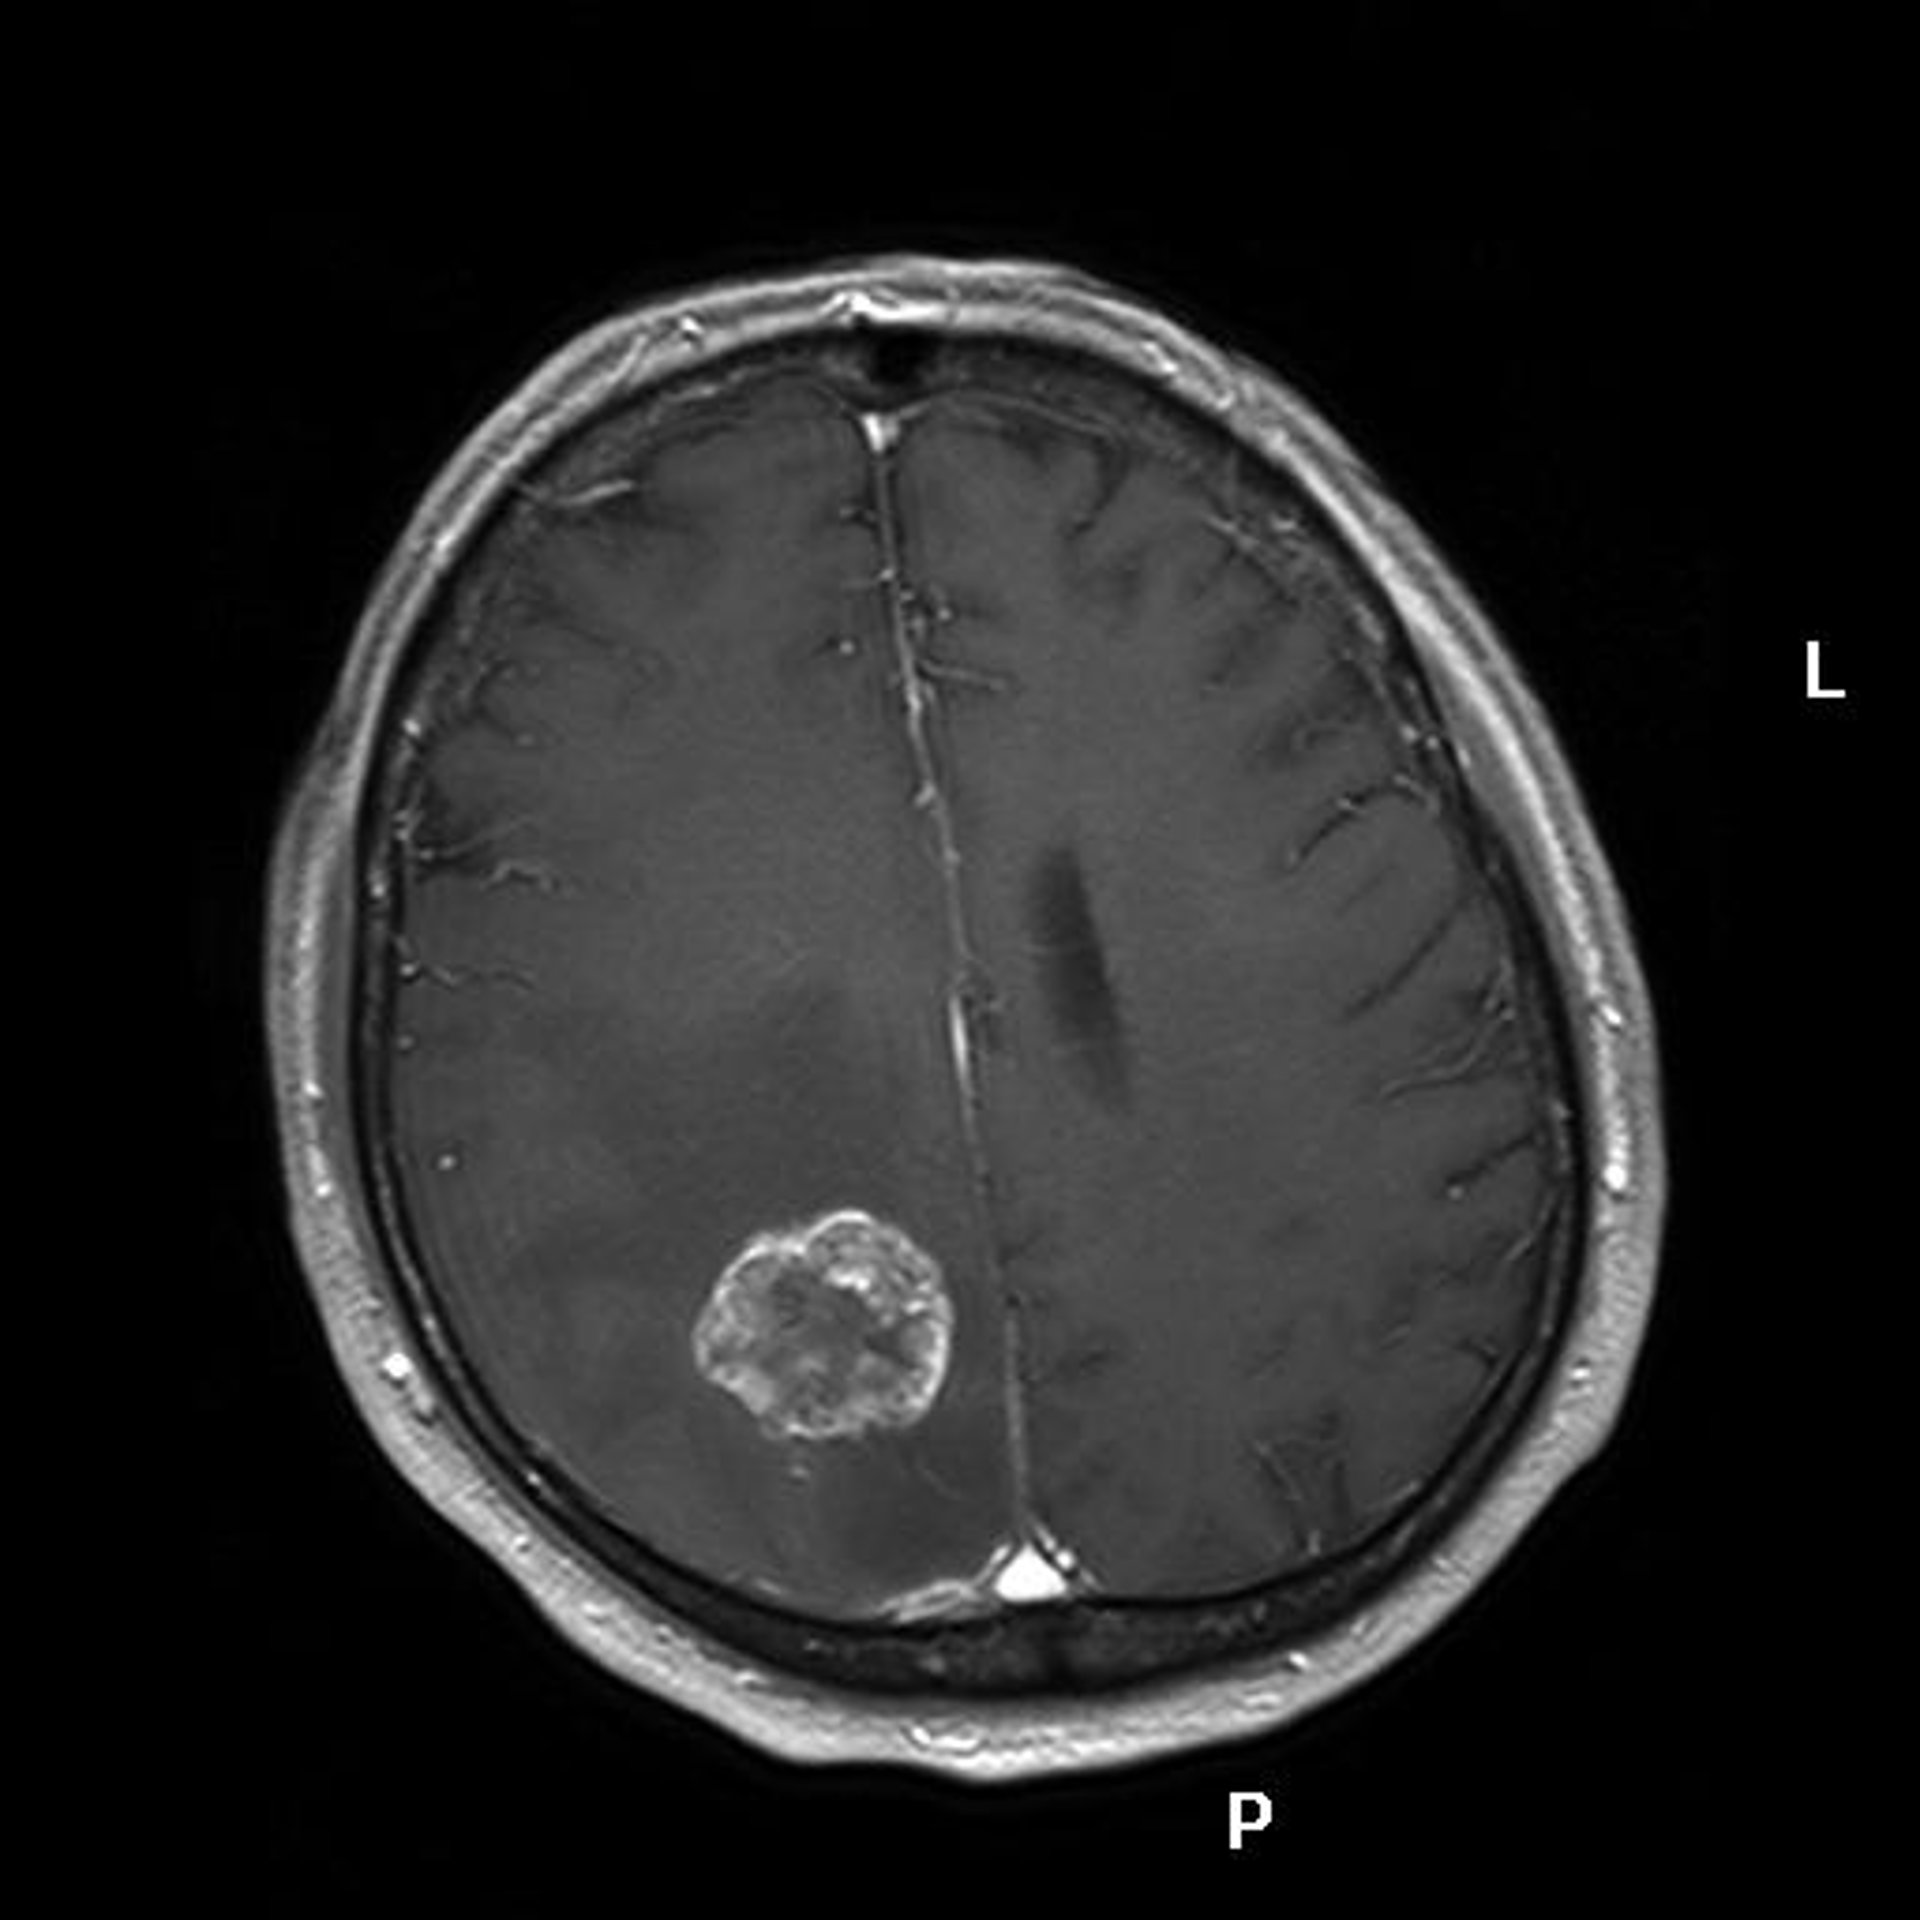

Cáncer, Tumor, Metástasis

MARVIN 101/WIKIMEDIA COMMONS